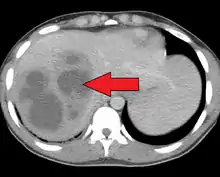

Pyogenic liver abscess

A large pyogenic liver abscess presumed to be the result of appendicitis

A pyogenic liver abscess is a type of liver abscess caused by bacteria.